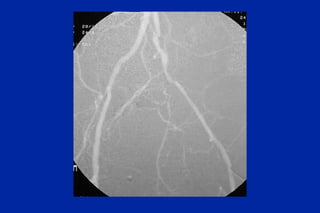

Este documento resume los principales tipos y técnicas de angiografía. Describe brevemente la angiografía, arteriografía, flebografía y linfografía, así como las técnicas de contraste y materiales utilizados. También explica los principales accesos vasculares, la técnica de Seldinger, la angiografía por sustracción digital y algunas técnicas endovasculares comunes.